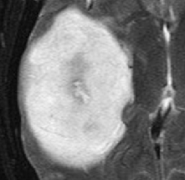

多形性胶质母细胞瘤(Glioblastoma multiforme,GBM)是成人较常见的恶性原发性脑肿瘤,是胶质瘤的较高分级。GBM患者的中位生存时间约为1年。然而,一小部分患者...

胶质母细胞瘤(glioblastoma multiforme,GBM)是较常见的颅内原发性恶性肿瘤,占原发性脑肿瘤的80%,多见于老年人,其中65岁以上的人群占50%。胶质母细胞瘤是国际卫...

胶质母细胞瘤 是一种高度恶性的脑肿瘤,起源于神经系统中的支持细胞--星形胶质细胞。正常情况下,星形胶质细胞负责多种角色,包括为神经元提供营养...